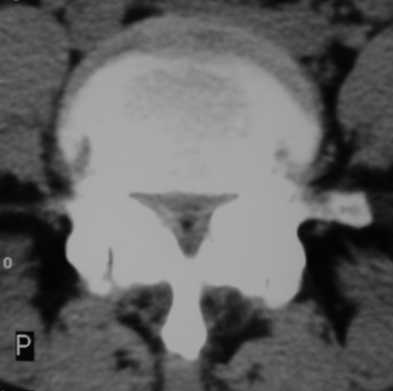

(2)腰椎管狭窄症的CT表现

在CT扫描的不同的横断面上,可观察到椎间盘膨出或突出,脊髓内可有囊性改变。